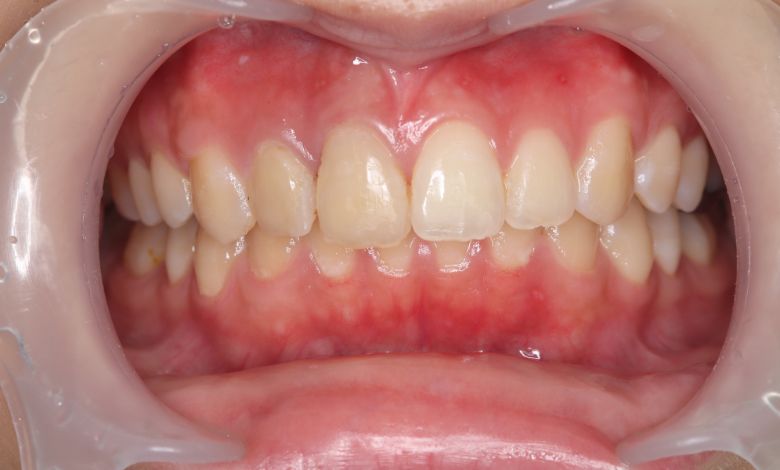

上下の歯がしっかりと噛み合う、美しい咬合(こうごう)が得られた

上下の前歯の重なりが解消され、歯軸の傾きも整いました。咬合関係も安定しています

上下の前歯の重なりや段差は完全に解消され、咬合関係も安定してる。自然なスマイルラインが形成され、口元の印象も大きく改善された

当院では抜歯を行わず、歯列弓を広げてスペースを確保する治療を選択。歯並びは自然なU字型へと整い、前歯の重なりも解消されました。咬み合わせが改善され、見た目の美しさはもちろん、咀嚼機能や清掃性の向上といった機能面でも良好な結果が得られています。